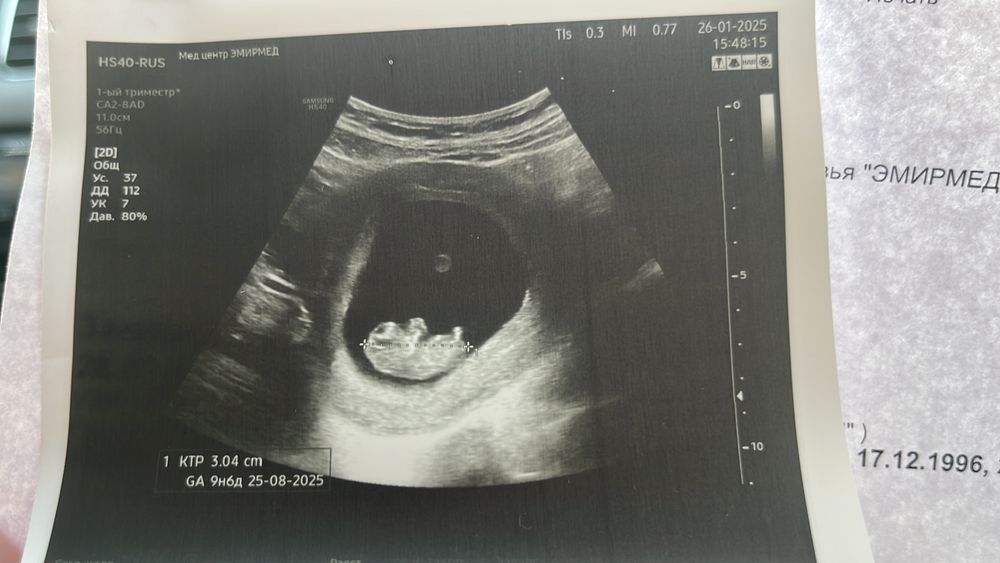

УЗИ на 10 неделе

Круглый красивый шарик- это желточный мешочек, который питает вашего малыша. Только к середине беременности плацента и пуповина заработают в полную силу. У меня 12-13 недель, желточный мешочек тоже есть

Была на УЗИ в 10н6д точно такая же картина как у вас, и такой же круглый шарик в центре, ещё писали про жм, при чем увидела его не сразу, на скрининге в 11н6д про жм уже в УЗИ не слова. СВДПЯ в 10н6д было 53 мм

Это не желтый мешочек? Он питает эмбриона, пока не сформировалась плацента

Яркость, в заключении почти ничего нет, пя не замерили, ктр 31 почти, срок на 9н5, пя изначально был больше, но смущает пузырек